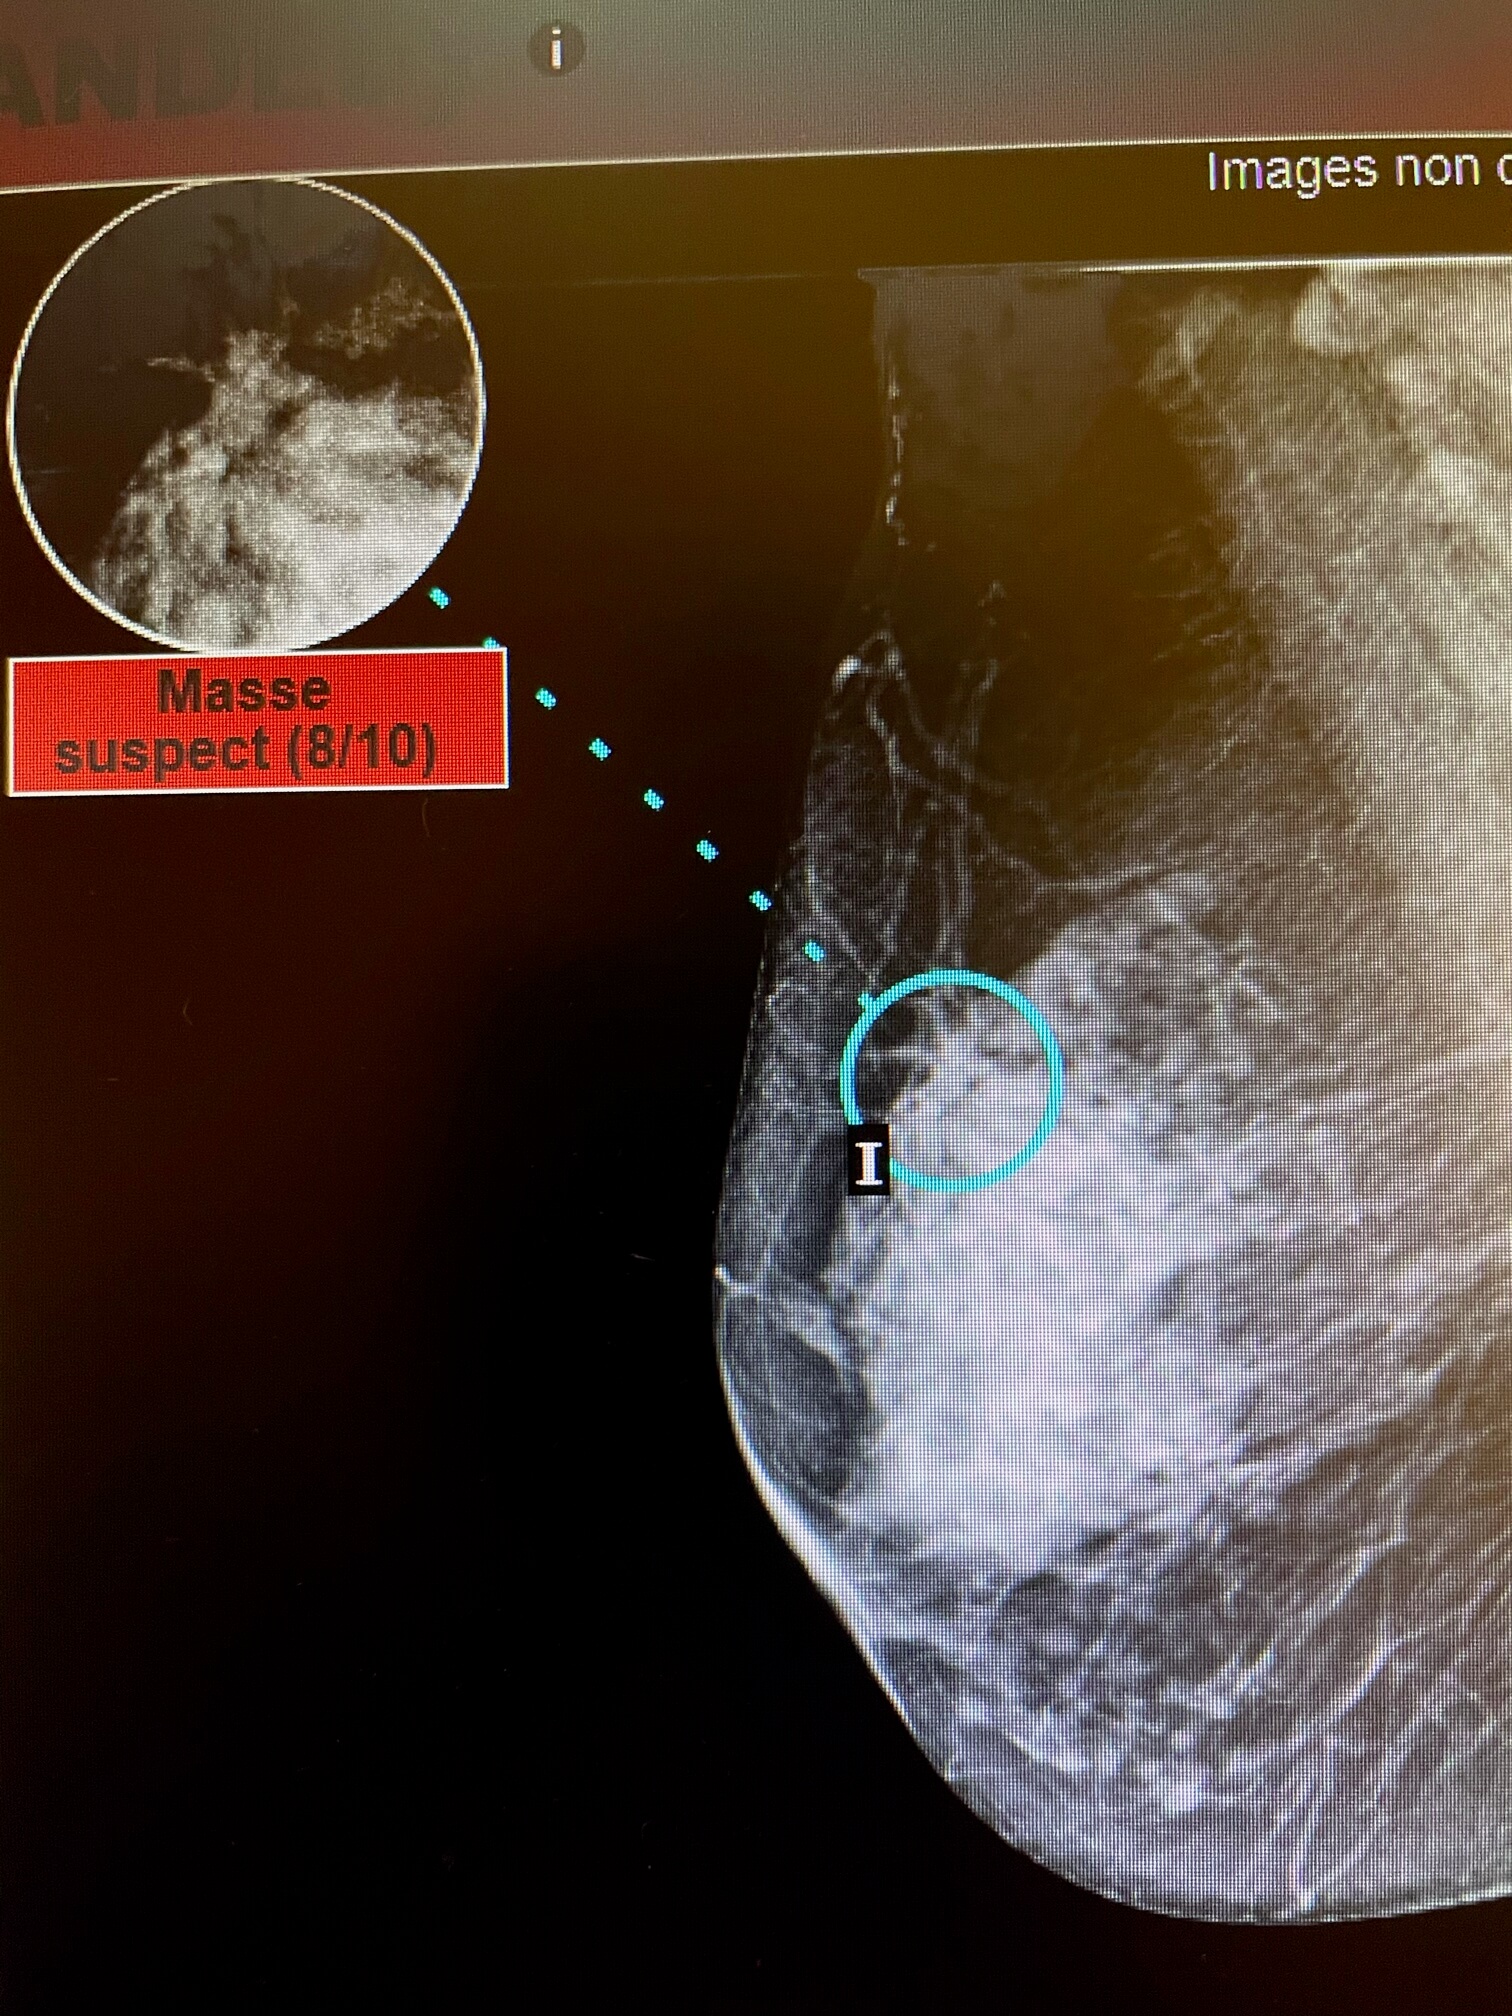

Case of the week (week 10, 2021)

65-year-old patient, screening mammogram.

MammoScreen® shows an architectural distortion of the right breast.